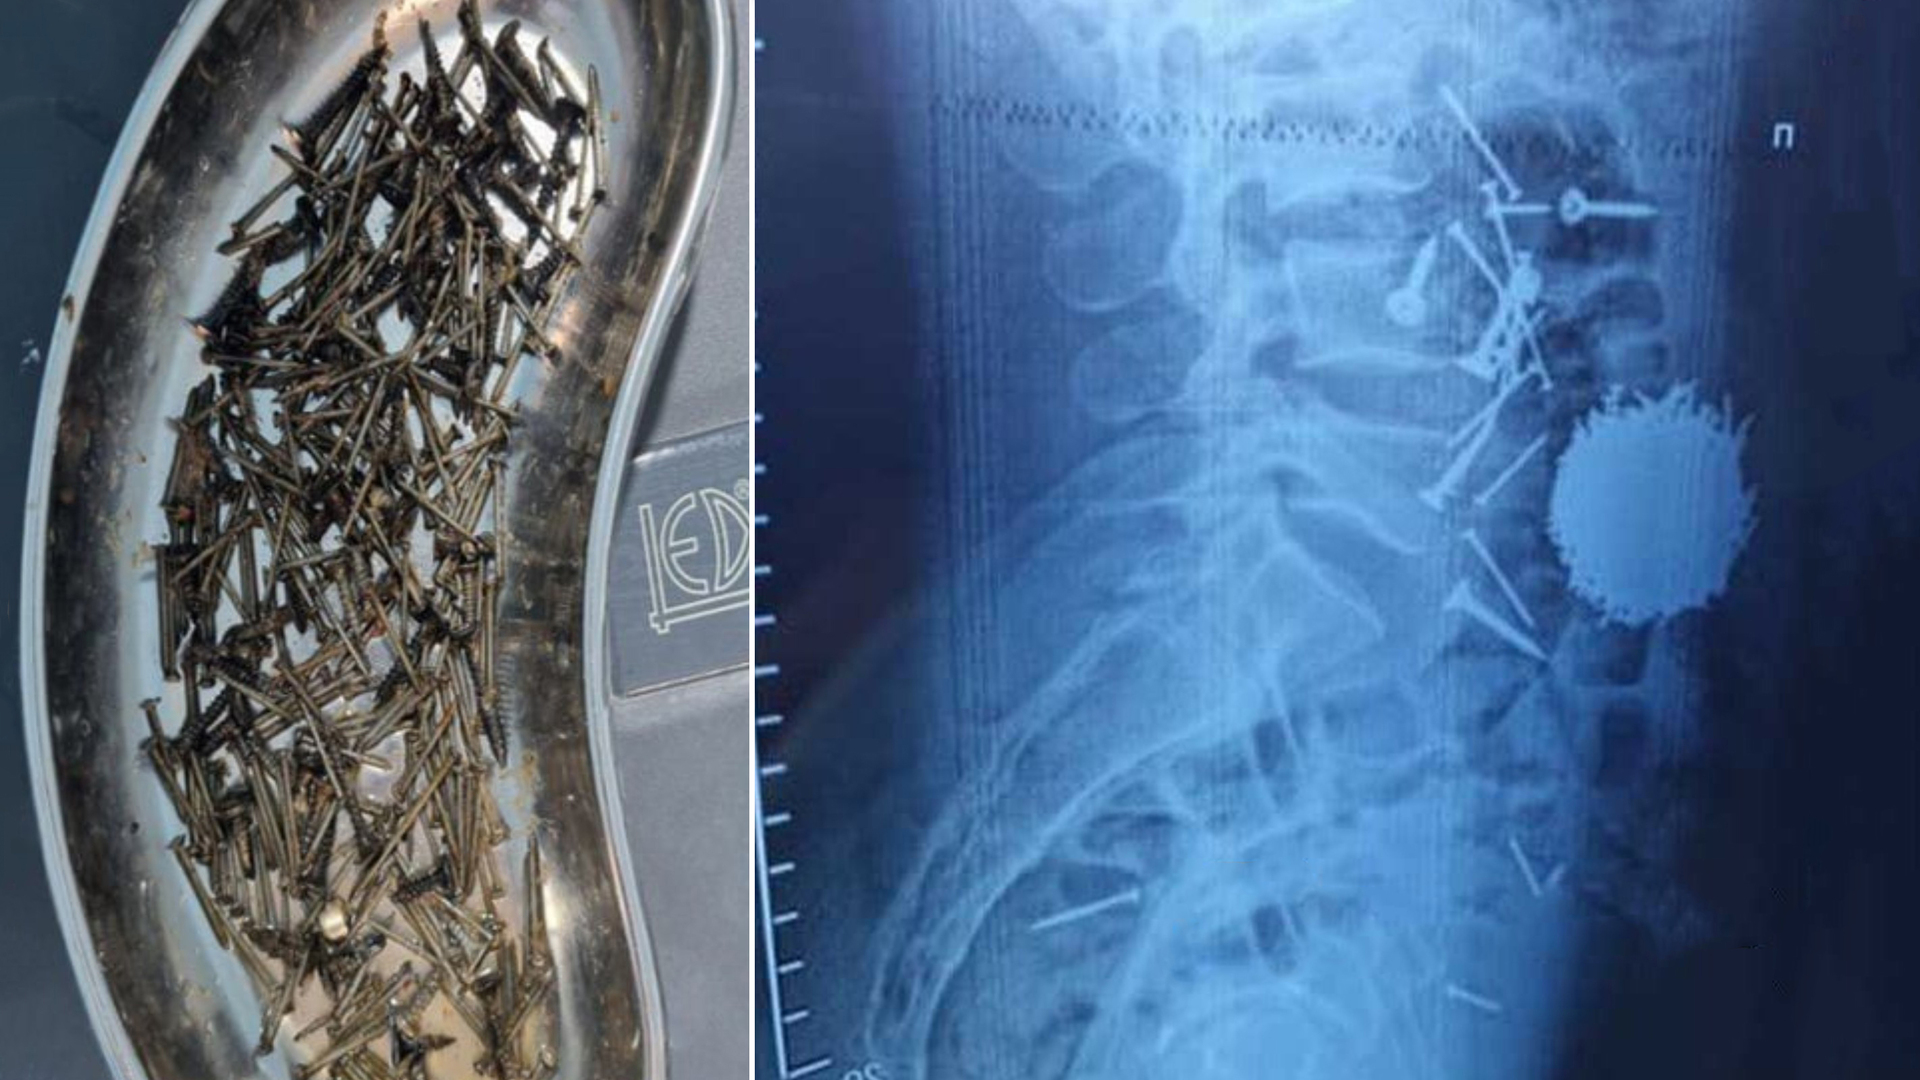

По результатам диагностики и лабораторных исследований у пациента в желудочно-кишечном тракте было выявлено большое количество металлических предметов — гвоздей и саморезов.

«Было принято решение о необходимости проведения экстренного хирургического вмешательства. После выполнения всех подготовительных процедур была проведена операция методом лапаротомии и гастростомии. Из брюшной полости пациента удалось извлечь значительное количество металлических предметов — около 200 граммов. Операция длилась около часа», — сообщил врач высшей категории медцентра Юлдош Кулиев.